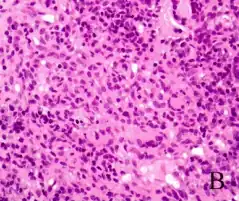

Systemic vasculitides are a group of heterogeneous diseases that share the etiology in terms of inflammation of the blood vessels (vasculitis) – more specifically the arterioles – with systemic envolvement. Some examples of this group include granulomatosis with polyangiitis, polyarteritis nodosa, Behçet's disease, and HSP.[1][2][3][4][5]